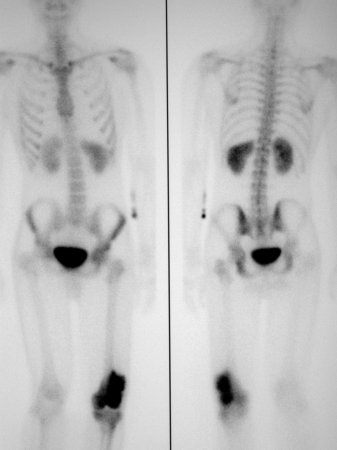

Osteossarcoma

Cintilografia óssea; alta captação de radionuclídeo no local do tumor

Do acervo do Dr. Michael J. Klein e da Dra. Luminita Rezeanu